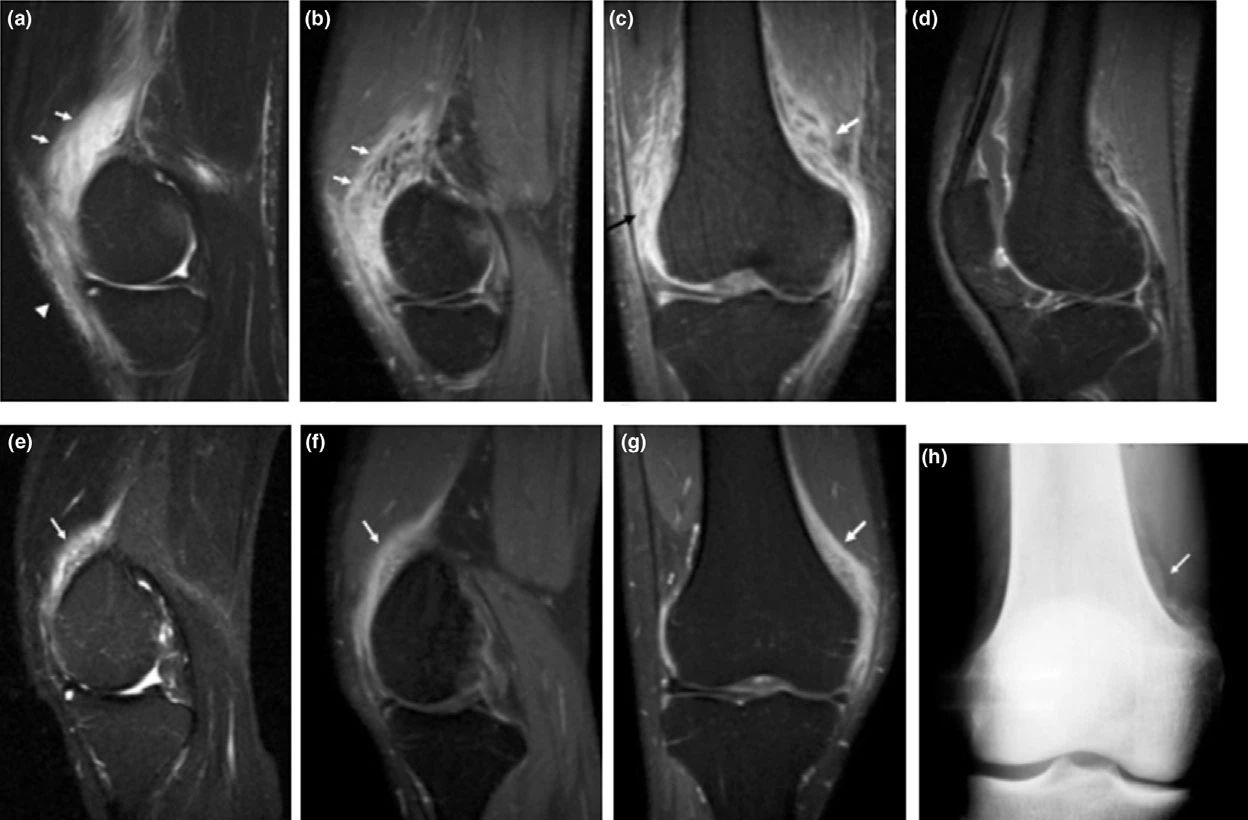

MRI 具有良好的软组织对比度,表现与疾病的时间相关,并且与其他影像平行,急性期 ,主要为软组织肿块合并周围水肿,病灶在 T1WI 上与肌肉呈等信号或稍高信号,在 T2WI 上以高信号为主。中期,T1WI 和 T2WI 信号都可减低,可以在病灶内部看到扭曲了的长T1 脂肪层,病灶边缘的钙化表现为低信号环,后期低信号环将越来越清楚,这也是异位骨化的特征性表现之一;此时 X 线平片可以看到皮质边缘。

后期,界限清楚的信号不均匀肿块,无水肿,在肿块中心可以 T1 呈高信号,表示脂肪化的黄骨髓形成,外围一圈 T1、T2 扭曲的低信号,代表骨化的皮质骨,此时期 MRI 的诊断价值不如 X 线和 CT,需要结合二者观察。

早期异位骨化:该患者颅脑损伤并且合并膝关节创伤,首次检查(a-d)股内侧肌周围T1高信号,皮下脂肪水肿,压脂呈花边样改变;3 周后复查(e-f)病灶内层不均匀强化,平片可以看到骨化及骨膜反应。

晚期异位骨化:患者受伤后 9 个月因关节强直复查,注意病灶周边清楚的低信号环。